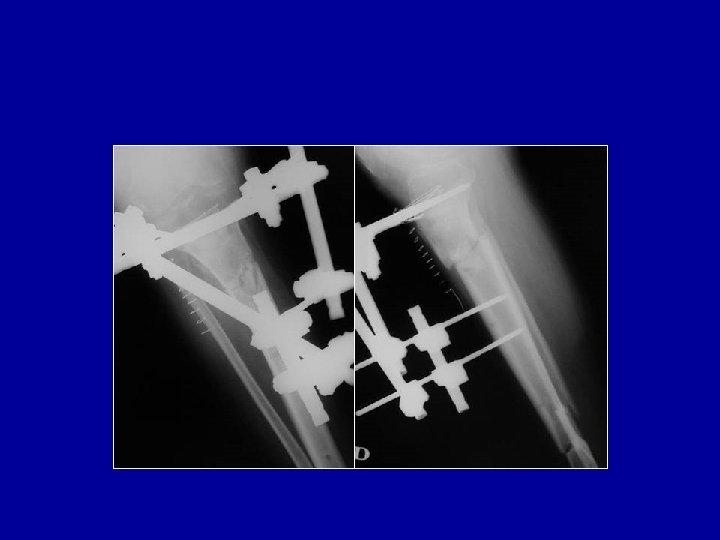

Traitement d’une fracture à double étage par fixateur externe avec montage sur le fragment intermédiaire

Traitement d’une fracture ouverte à double étage par fixateur

Le fixateur facilite le traitement des lésions cutanées

Cas particulier des fractures métaphysaires ouvertes Les broches sont difficiles à placer dans une épiphyse

Cas particulier des fractures métaphysaires ouvertes Les broches sont difficiles à placer dans une épiphyse Fixateur de Sheffield

Cas particulier des fractures métaphysaires ouvertes Ostéosynthèse a minima de l’épiphyse et de la métaphyse et mise en place d’un fixateur à distance

Cas particulier des fractures métaphysaires ouvertes Ostéosynthèse a minima de l’épiphyse et mise en place d’un fixateur. Quand le péroné est déplacé, une plaque est possible si la peau est intacte en dehors En cas de perte de substance osseuse, on fera une greffe secondairement

Cas particulier des fractures métaphysaires ouvertes